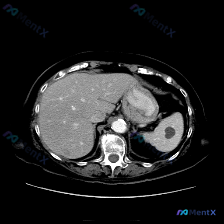

整理了一份腹部CT发现脾脏低密度结节的读片思路,分享给大家一起讨论。 先看影像表现(单幅平扫CT) - 肝脏:形态尚可,密度基本均匀,未见明显局灶性占位 - 脾脏:重点!脾脏大小形态正常,实质内靠近后缘可见一处圆形低密度小结节,边界尚清,密度接近水,无明显周围浸润或占位效应 - 其他:胃壁、脊柱、腹...